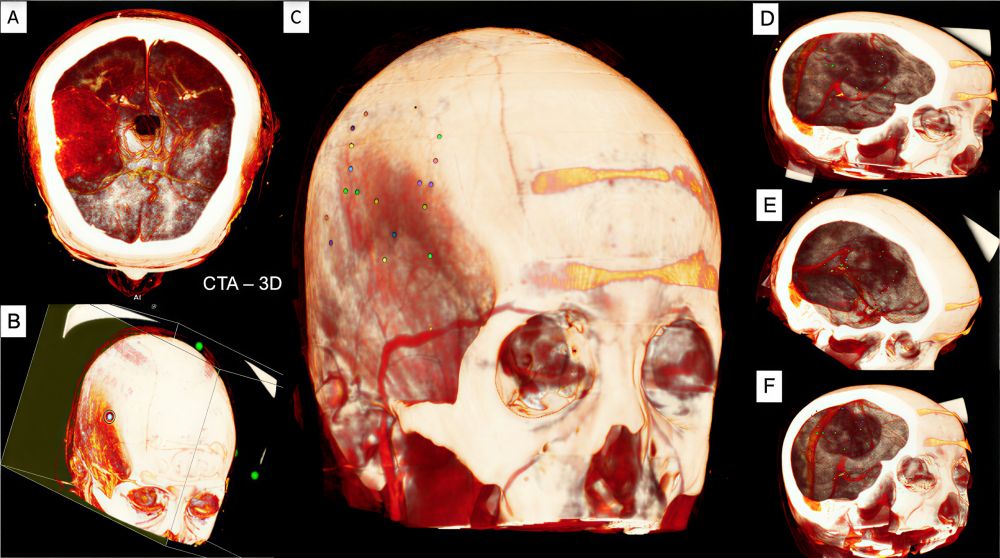

Hình 1. Tái tạo hình ảnh 3D khối u não vùng trán thái dương phải (A, B) với cấu trúc xương, mạch máu xung quanh, đồng thời xác định vị trí u bám trên bề mặt xương vùng thái dương phải và dựa vào mặt cắt mô phỏng để dự đoán vị trí u, các mạch máu nuôi u để lên kế hoạch phẫu thuật (C-F)

CTA (CT angiography) hoặc DSA (Digital Subtraction Angiography): dùng trong các trường hợp u lớn, tăng tưới máu, giúp xác định nguồn cấp máu nuôi u, hỗ trợ tắc mạch trước mổ nếu cần.

Tái tạo 3D (Three-dimensional reconstruction): công cụ hiện đại giúp phẫu thuật viên mô phỏng không gian giải phẫu giữa khối u – hộp sọ – mạch máu, lựa chọn đường mổ và bản xương tối ưu.

Tại Bệnh viện Trường Đại học Y Dược Huế, kỹ thuật tái tạo 3D bằng phần mềm Horos đã được ứng dụng thường quy, mang lại hiệu quả rõ rệt trong lập kế hoạch phẫu thuật u lớn và u nền sọ giúp phẫu thuật viên có thể lập kế hoạch mổ chính xác, giảm biến chứng và tối ưu hóa kết quả điều trị.

CT sọ não cho thấy khối choán chỗ vùng thùy trán phải, kích thước 71×50×50 mm, gây phù não lan tỏa và lệch đường giữa 13 mm. Chụp CTA xác định nguồn cấp máu từ nhánh động mạch não giữa phải, các tĩnh mạch vỏ não và xoang dọc trên vẫn lưu thông. Dữ liệu CTA được xử lý bằng phần mềm tái tạo 3D (Horos) giúp xác định mối tương quan giữa khối u, hộp sọ và mạch máu, hỗ trợ lựa chọn vị trí mở sọ tối ưu.